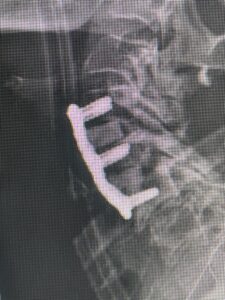

(Fig 3) lateral intraoperative cervical x-ray demonstrating good alignment after C4-C6 anterior cervical discectomy and interbody fusion with plate. Note the interbody grafts help load-share the plate in this patient with severe osteoporosis

This 59 year-old female had severe bilateral leg pain and numbness over a 6-month period. The patient had failed conservative treatment with physical therapy, chiropractic care, and medications. MRI revealed that she had severe lumbar stenosis with a grade 1 spondylolisthesis or “slipped disc” at L5-S1 (Fig. 2). In addition, she had previously undergone both front and back surgery for severe cervical stenosis where her posterior hardware had failed because of her severe osteoporosis requiring us to remove the posterior hardware. This required her to have an anterior or front operation which allowed better fixation to her spine because of the load-sharing nature of the interbody grafts in addition to her anterior cervical plate (Fig. 3).